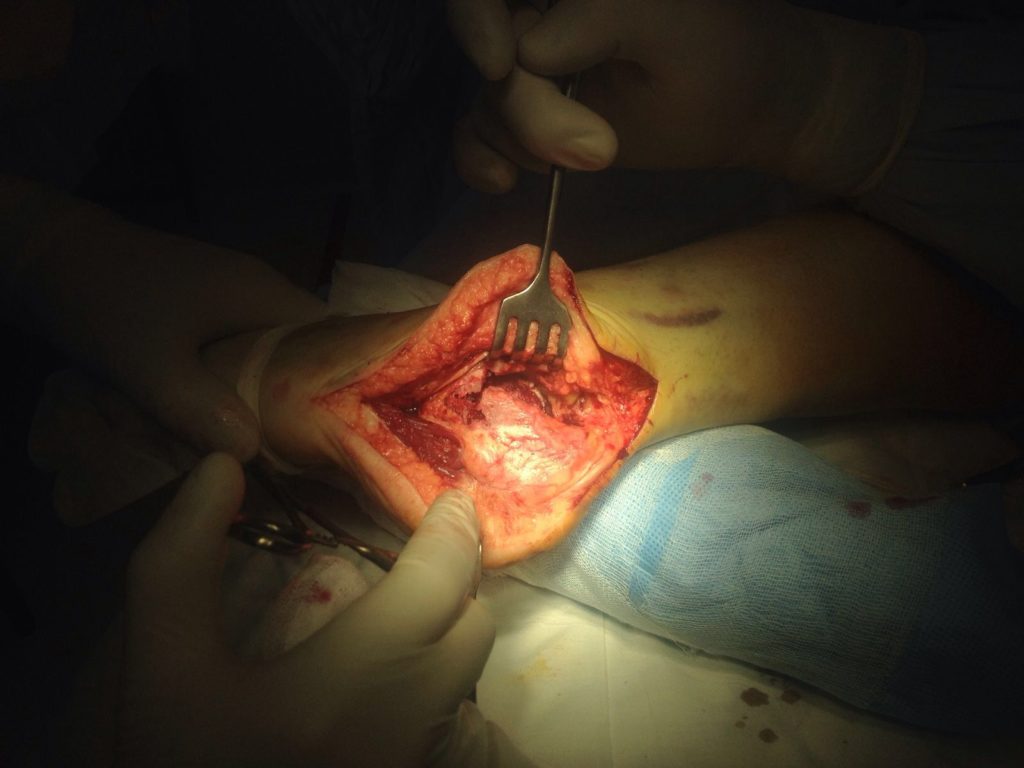

Применение материала Остеоматрикс при импрессионно-оскольчатом переломе пяточной кости

Операция – открытая репозиция, остеосинтез пяточной кости пластиной с костной ксенопластикой материалом «Остеоматрикс». На контрольных снимках в три месяца имеется консолидация перелома, миграции фиксатора нет, имеется остеоинтеграция ксенопластического материала.